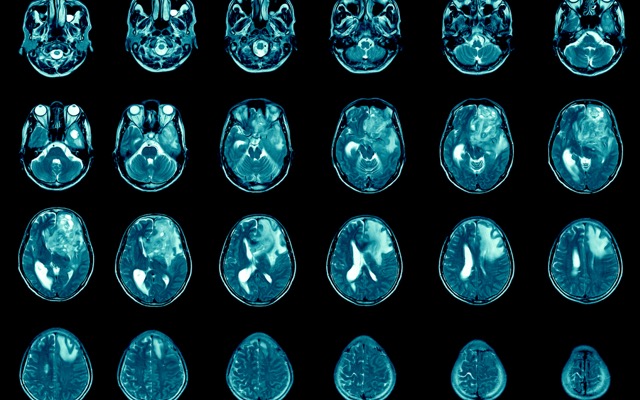

GBM AGILE is a global, academic-led study designed to identify promising new therapies for glioblastoma, which is the most common and most aggressive form of primary brain cancer in adults.

Paxalisib is a brain-penetrant inhibitor of the PI3K / Akt / mTOR pathway and is being developed to treat glioblastoma.